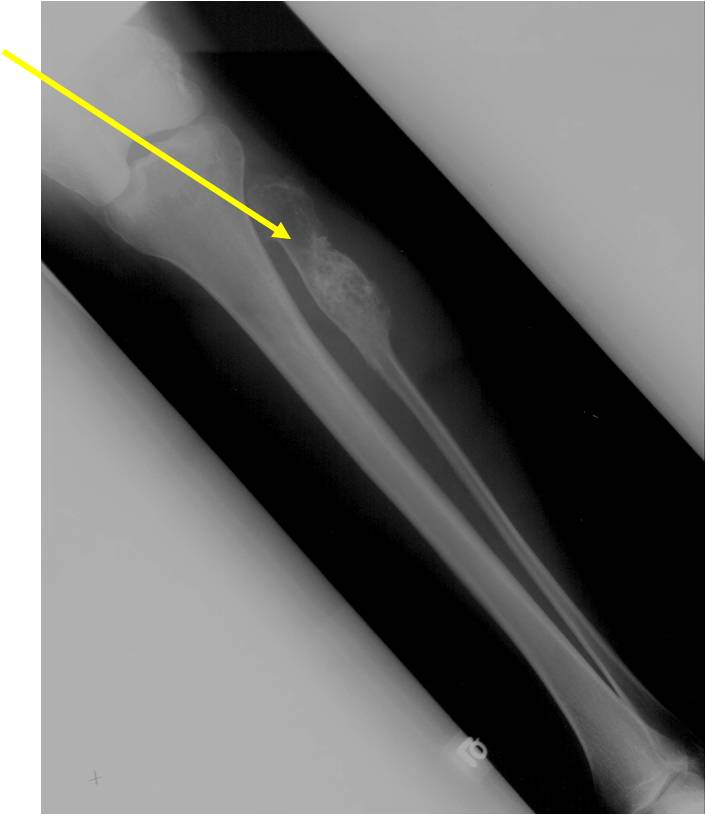

- Localized, radiolucent defect usually with punctate calcifications

- Calcifications are stippled, punctate, popcorn like calcifications and “Ring and Arc” calcifications

- Cortex may be scalloped and thinned in the phalanges

- Expansile remodeling with thinned cortex

- Chondroid matrix with calcifications in majority of tumors

Enchondromas in enchondromatosis may involve the metaphysis, diaphysis, epiphysis and articular cartilage